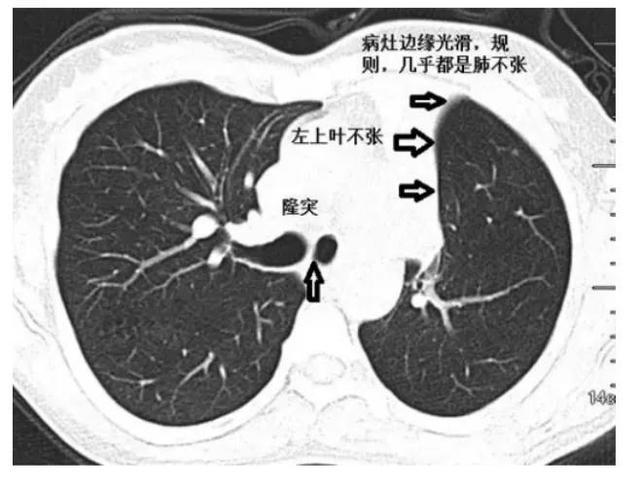

肺不张影像图片,肺不张影像

肺不张的影像学

肺不张:影像基本思路

肺不张影像表现

肺不张ct图片

肺不张影像学表现

肺不张ct表现图片

肺不张ct经典图片

肺不张ct

肺不张ct表现